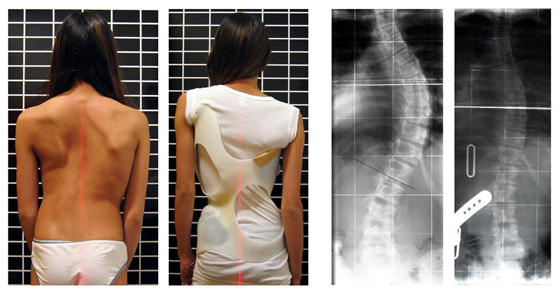

โรคกระดูกสันหลังคด (Scoliosis) คือ อาการที่กระดูกสันหลังของเรามีรูปร่างคดงอบิดผิดปกติ แทนที่จะมีรูปร่างตรง เมื่อมองจากด้านหลัง โดยมีรูปแบบการคดงอ 2 แบบคือ คดเป็นตัว C คือ มีจุดคดแค่จุดเดียว และ คดเป็นตัว S คือมีจุดคดสองตำแหน่ง จนดูคล้ายตัว S ถ้าเป็นเล็กน้อยก็ไม่กี่องศา แต่ถ้าเป็นหนักก็คดได้ถึง 90 องศาเลยล่ะ!

ผู้ป่วยกระดูกสันหลังคดในประเทศไทย มีมากถึง 2-3% ของประชากรเลยทีเดียวค่ะ ความน่ากลัวของโรคนี้คือ เป็นกันโดยไม่รู้ตัว และเริ่มเป็นในช่วงวัยเด็ก ถ้าไม่ได้รับการรักษาโดยแพทย์เฉพาะทาง จะมีผลกระทบต่อสุขภาพ ถ้าปล่อยให้คดมากขึ้นเรื่อยๆ นอกจากจะบุคลิกเสียแล้วยังกระทบกับอวัยวะภายใน เช่น ระบบทางเดินหายใจ ระบบหัวใจ จนถึงขั้นเสียชีวิตได้ เพราะหายใจไม่สะดวกและหัวใจทำงานหนัก

สำรวจตัวเองแล้วเจอว่าเป็นข้อใดข้อหนึ่งในนี้ พี่มิ้นท์แนะนำว่ารีบไปหาหมอเฉพาะทางเลยเพื่อเอ็กซเรย์ดูกระดูกสันหลังโดยด่วน เพื่อทำการรักษาต่อไปค่ะ เพราะถ้าคดน้อยก็ยังมีวิธีการรักษาด้วยการใส่เสื้อเกราะดัดหลังได้ แต่ถ้าคดมาก ต้องหาหมอเพื่อผ่าตัดอย่างเดียว

เราเป็นเคสตัวSตอนนี้รักษาตัวที่โรงบาลกรุงเทพจ้า คดหนักยังไงหาหมอปรึกษานะแต่ส่วนใหญ่เกินสี่สิบห้าสิบขึ้นหมอหลายที่แนะให้ผ่า แต่หมอชนิณแนะให้ดัดดูก่อนจากเคสศึกษาเด็กและวัยรุ่นไทยเป็นเยอะมากดัดองศาก็ลดลงหลายสิบอยู่

เราเป็นตอนม.1ใส่เสื้อเกราะมา1ปี องศาลดน้อยมาก เคสเรา45องศาเป็นขั้นหนักแล้วนะ เลยตัดสินใจผ่าตัด ที่ผ่าเนี่ยก็ไม่ได้ตรงเป็นปกตินะยังคตนิดๆ20กว่าๆ มันก็จะคงที่ไปเลย~~(ตอนนี้ม.6แล้ว ก็หาหมอทุกปี)